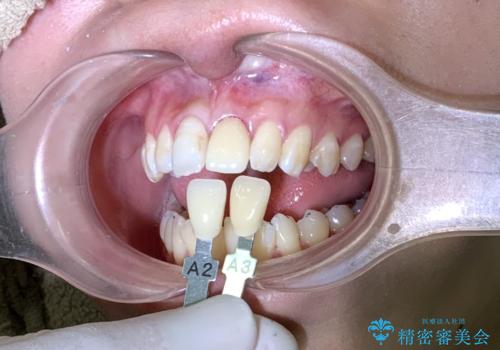

- 以前に前歯を強打し、変色してきた前歯の審美性の改善を希望されて来院されました。

X線検査の結果、変色をきたしている歯は根尖病変が存在し、神経が失活している状態でした。

根管治療を行ったのち、セラミッククラウンで審美性を改善していきます。